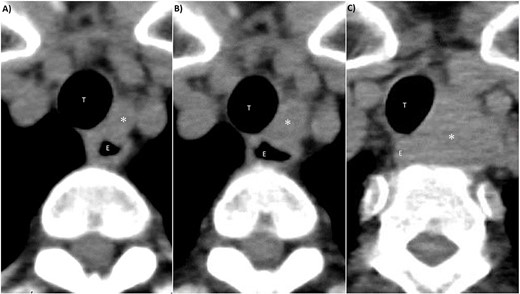

Pre-operative imaging findings of papillary thyroid cancer. (A) Ultrasonography revealed a hypoechoic 28-mm mass with internal calcification was found in the right lobe of the thyroid gland. (B) Contrast-enhanced CT revealed a 37 mm× 25 mm tumor in the right lobe of the thyroid gland without surrounding invasion and no lymph node metastasis or distant metastasis. *: tumor, CA: carotid artery, IJV: internal jugular vein, T: trachea, E: esophagus.

CT findings of left III lymph node metastasis. (A) 4 years after initial surgery, size: 9 mm × 7 mm. (B) 5 years after initial surgery, size: 14 mm × 10 mm. (C) 7 years after initial surgery, size: 32 mm × 27 mm. *: left III lymph node, T: trachea, E: esophagus.